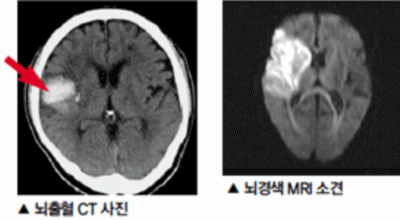

뇌경색의 경색이란 허혈성 괴사를 말해요. 여기서 허혈이란 혈관이 막히는 것을 말하고 괴사는 말 그대로 일부가 죽는 것을 말하는데 뇌경색의 경우 뇌의 혈관이 막혀 뇌세포 일부가 죽는 걸 의미해요. 뇌혈관이 막혔다 해서 혈액 공급이 안되는것은 또 아니에요.

막힌 혈관으로도 혈액이 공급되긴 하나 혈관이 막혀있어 혈액을 보내긴 하나 제대로 흐르지 못하고 혈액이 쌓이고 축적되어 물풍선에 물이 꽉 차서 터지듯 뇌혈관이 터지는 경우가 일어날 수 있는데 이를 뇌출혈 이라고 해요. 물론 외상으로 인한 뇌출혈도 있지만 이처럼 뇌경색으로 인해 혈관이 막혀 터지는 경우도 있어요.